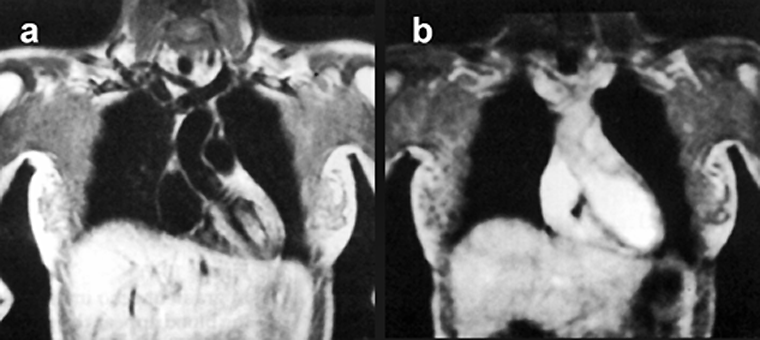

Figure 14-10 shows that in the spin-echo image, flowing blood within the heart cham­bers and the ascending aorta is black, whereas in the gradient-echo image, flow­­ing blood appears bright.

Figura 14-10:

Effects of blood flow upon signal intensity in a (a) spin-echo and a (b) gradient-echo pulse sequence.